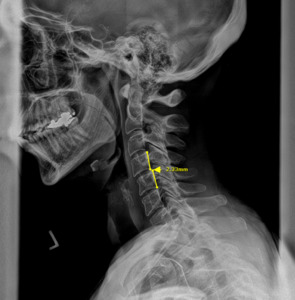

Plain film radiography of the cervical spine showed a grade 1 spondylolisthesis of C4 (Figure 3), mild disc and facet degeneration of C5 (Figure 3), a motion fixation of the C4-C5 vertebrae unit in forward flexion (Figure 4), a retrolisthesis of C3 on extension (Figure 5), and a structural malposition of the craniocervical junction as per Orthospinology measurements. (Figures 6 and 7). Though these are static films and active motion cannot be observed in real-time, motion restriction of the C4-C5 vertebrae unit from neutral to forward flexion position was determined by a lack of spinous separation, a lack of intervertebral foramen expansion, and an absent intersegmental kyphosis of George’s Line.

During the initial examination, the chiropractor evaluates the patient’s postural findings, including standing head tilt, head rotation, shoulder height comparison, hip height comparison, lower neck deviation, and supine leg-length inequality. The chiropractor will then take 3 radiographic images of the CCJ minimum to view the alignment in a projected 3-dimension. These images are the cervical neutral lateral (sagittal plane), the nasium (frontal plane), and the vertex (transverse plane). A series of measurements are graphed on the radiographs to assess for alignment. Then, the Orthospinology upper cervical procedure provides a calculation and vectored angle based on these measurements to reduce the misalignment. The chiropractor will use this angle to administer the adjustment to the CCJ. Immediately after the adjustment, the chiropractor evaluates the postural findings for correction. If it has improved, the chiropractor repeats the nasium and vertex views to observe for structural correction. If the postural findings do not improve, the chiropractor may administer a subsequent adjustment before the post-imaging is taken.12